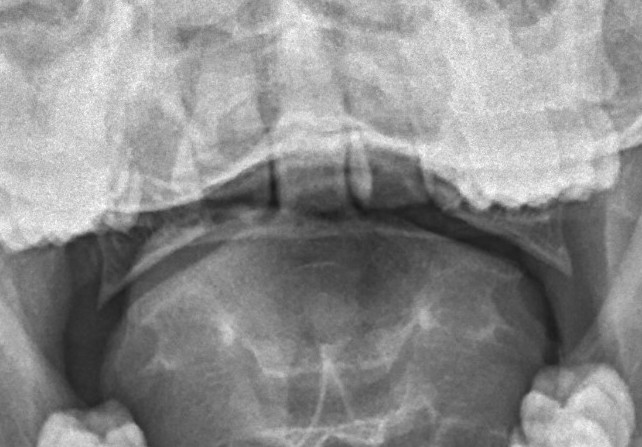

X-ray

1.  Lateral mass displacement (LMD)

Open mouth odontoid view

- sum of lateral mass displacement

- increased LMD suggests TAL injury

Kopparapu et al J Neurosurg Spine 2022

- Rule of Spence:  LMD > 6.9 mm predicts TAL injury, instability and need for surgery

- developed in 1970's

- inaccurate in predicting TAL injury

Eun et al Medicine 2021

- LMD > 8 mm seen in 90% of patients with transverse ligament injury

LMD

Lateral mass displacement

LMD 1LMD 2

Increased lateral mass displacement of 8 mm